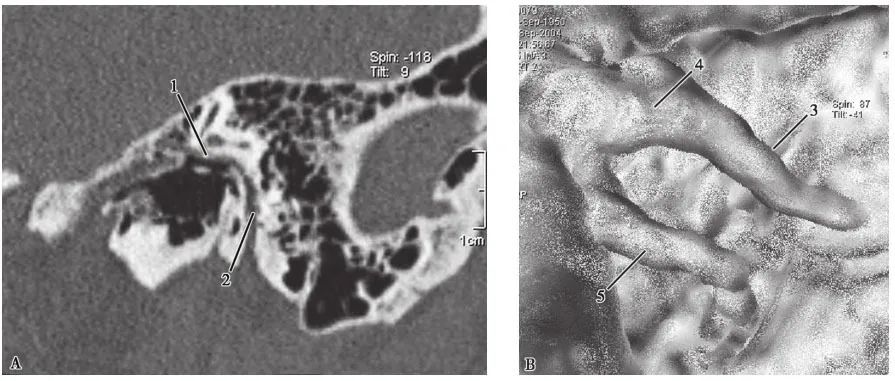

特殊后处理CT图像

A.面神经管MPR图像;B.鼓室CTVE图像;C.VR图像1.面神经管鼓室段;2.面神经管乳突段;3.锤骨柄;4.锤骨颈;5.砧骨长脚;6.砧骨;7.锤骨;8.半规管;9.耳蜗